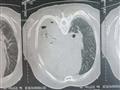

أجرى الأطباء في مستشفى دسوق العام، بكفر الشيخ، أول عملية من نوعها لشق صدر مريض مسن، في ظل الإمكانيات المحدودة، التي تعاني منها أغلب المستشفيات الحكومية.

وقاد الدكتور وسيم عطية، أستاذ مساعد جراحة القلب والصدر، بطب جامعة الأزهر، فريقًا طبيًا، ضم الدكتور أحمد عليبة استشاري التخدير، وعددًا من طاقم التمريض، والعاملين، لإجراء الجراحة، لرجل عجوز يبلغ من العمر 72 عامًا، يقيم بإحدى القرى التابعة لمركز دسوق، تعرض لحادث سير، أسفر عن إصابته بكسور متعددة، في الضلوع ونزيف بالصدر، وتهتك بالرئة.

وبدأ الفريق الطبي، مهام عمله بتركيب قسطرة، تصريف صدر، لتفريغ النزيف، وجرى حجز الحالة بالعناية المركزة، وعمل الفحوصات الطبية اللازمة، حتى تقرر له إجراء الجراحة، والتي استغرقت حوالي 5 ساعات متواصلة، عبارة عن شق الصدر بالكامل، وإصلاح بعض الضلوع فيه، وكذا إصلاح جدار الصدر، وتقشير القشار البلوري، وأيضًا إصلاح تهتك الرئة.